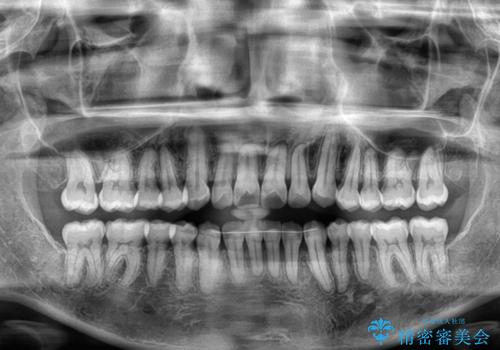

前歯のクロスバイト インビザラインによる矯正治療

- 上下のクロスバイトと前歯のデコボコを気にして来院された患者様です。

インビザラインを用い、IPR(歯と歯の間を削る)と歯列全体を拡大させることで、歯並びを整えていくこととしました。

インビザライン特有の、治療後半に奥歯が咬み合わないという事象が長引きました。

咬み合わないときの対処方法は色々とありますが、ゴムかけなどを活用して噛めるようにしました。